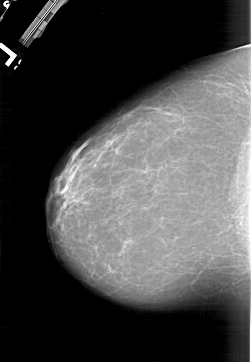

A_1177_1.LEFT_MLO

LEFT_MLO LINES 6871 PIXELS_PER_LINE 4126 BITS_PER_PIXEL 12 RESOLUTION 43.5 NON_OVERLAY